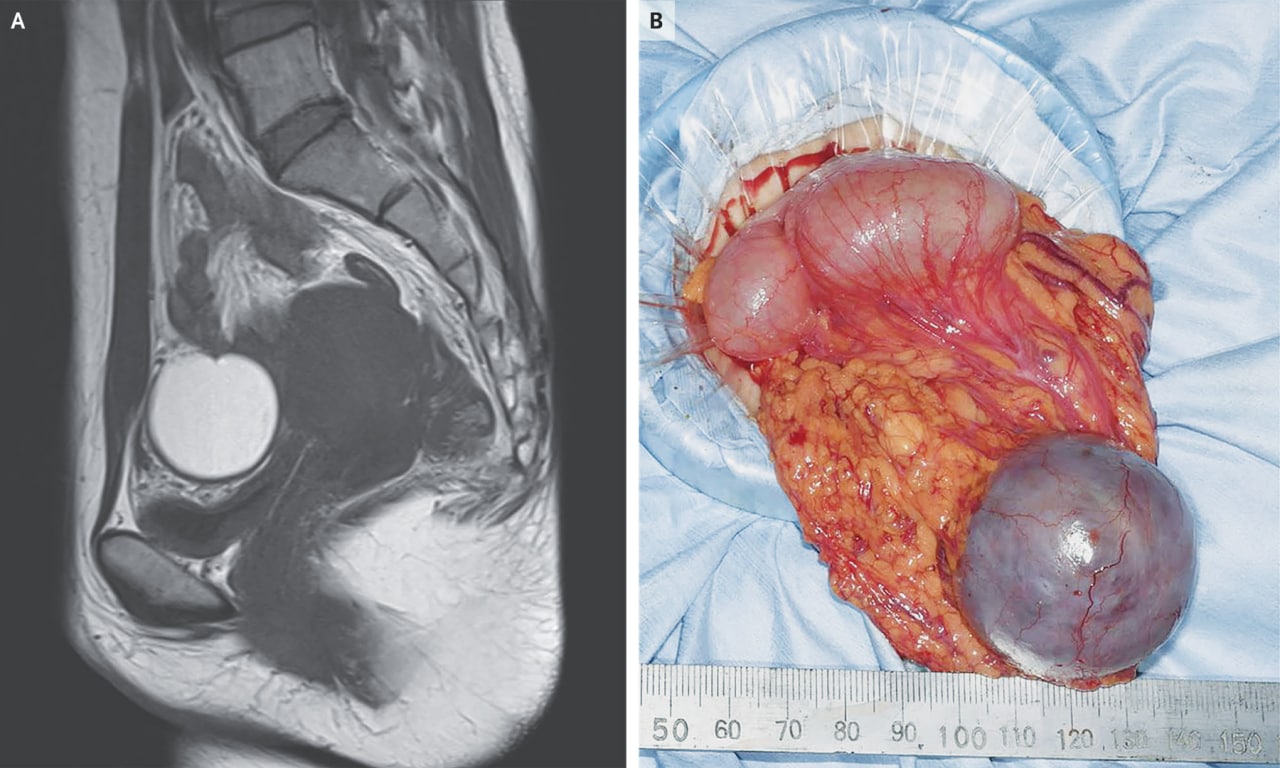

Клинический случай прямиком из Японии. Женщина 37 лет обратилась в гинекологическую клинику со спастической болью внизу живота, возникшей во время менструации. 5 годами ранее она проходила хирургическое лечение эндометриоза яичников.

Магнитно-резонансная томография выявила кистозную массу размером 4,1 см на 4,1 см на 4,1 см в нижней части живота, которая имела высокую интенсивность сигнала на Т1-взвешенном изображении (фото A). При выполнении лапароскопии (разрез брюшной полости) хирурги обнаружили, что образование имеет сальниковое происхождение (фото B; также видны петли кишечника). Матка и яичники задеты не были, образование удалили.

Патоморфологическое исследование вырезанного образования показало результаты, соответствующие эндометриозу. Эндометриоз сальника - это форма экстратазового эндометриоза. При контрольном обследовании через 1 месяц пациентка сообщила о прекращении болей в животе, а потом через 15 месяцев после операции успешно забеременела.